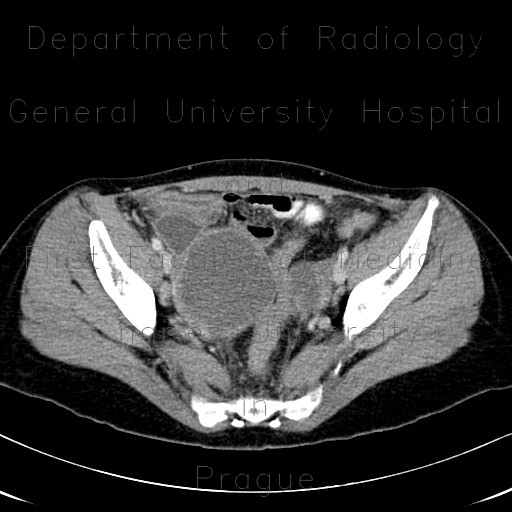

Endometriosis Ct : Endometriosis Different Locations And Faces Seen By Ct And Mri Semantic Scholar / Doi although several radiological techniques have been used for the diagnosis of bowel endometriosis, no gold.. It manifests in three ways; For patients with endometriosis, the ct scan may reveal endometrial lesions on the ureters or kidneys, or on the abdominal wall. Endometriosis is a condition where tissue similar to the lining of the womb starts to grow in other places, such as the ovaries and fallopian tubes. Endometriosis affects an estimated 176 million women worldwide regardless of their ethnic and many remain undiagnosed and are therefore not treated. Endometriosis happens when the endometrium, tissue that usually lines the inside of your uterus, grows outside it.

Endometriosis can affect women of any age. This can happen for several reasons: Jan hein van waesberghe, marieke hazewinkel and milou busard. There exist several stages of severity and its diagnosis can be complicated. Learn more about the types, symptoms, causes, diagnosis, stages, treatment. Human reproduction, vol 34, № 3. Doi although several radiological techniques have been used for the diagnosis of bowel endometriosis, no gold. Endometriosis is characterised by the growth of endometrial tissue. Possible causes, signs and symptoms, standard treatment options and means of care and support. Endometriosis is the abnormal growth of endometrial cells outside the uterus. Endometriosis is a common disease that can lead to female infertility in some cases. Endometriosis happens when the endometrium, tissue that usually lines the inside of your uterus, grows outside it. For patients with endometriosis, the ct scan may reveal endometrial lesions on the ureters or kidneys, or on the abdominal wall.

For patients with endometriosis, the ct scan may reveal endometrial lesions on the ureters or kidneys, or on the abdominal wall. This can happen for several reasons: Endometriosis is an abnormal growth of endometrial cells found in the uterus. Radiology department of the vu university medical center amsterdam, the netherlands. Jan hein van waesberghe, marieke hazewinkel and milou busard.